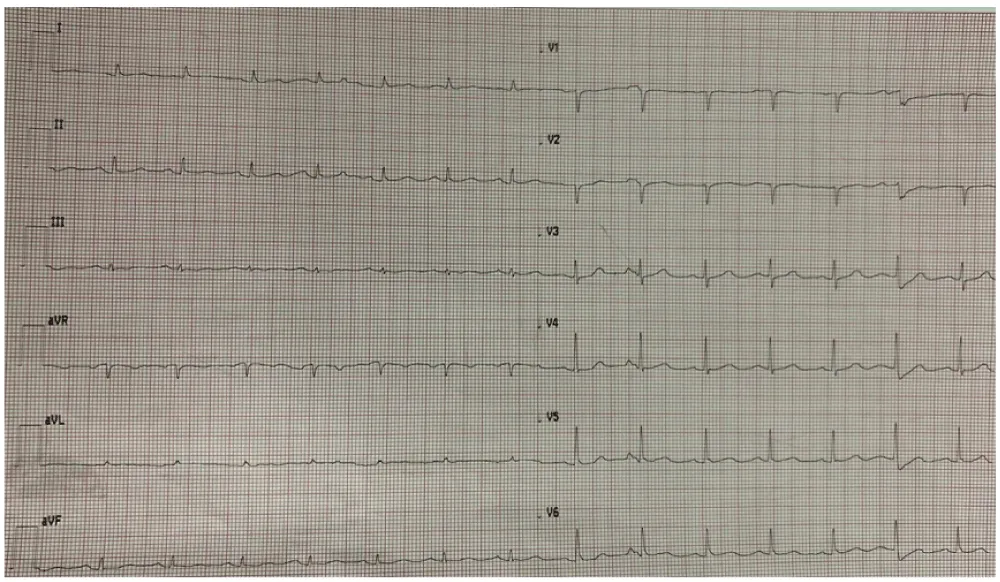

On ICU day 7, the ECG monitor showed significant QRS morphology changes. A 12-lead ECG (Image 4) revealed sinus rhythm at 85 bpm, PR interval 200 ms, normal axis, QRS 110 ms, ST-segment elevation in leads I, aVL, II, III, aVF, V5–V6, ST depression in V1–V4, and negative T waves in I, aVL, V5–V6. QTc was prolonged to 520 ms. Bedside echocardiography showed preserved biventricular function (LVEF 60%), no regional wall motion abnormalities were observed, no significant valvular disease, and a small, subacute pericardial effusion without signs of tamponade. Serial high-sensitivity troponin I levels were 42.5 ng/L and 43.5 ng/L three hours apart (Image 2). No dynamic changes were observed. Laboratory tests revealed metabolic acidosis (pH 7.21, HCO3 17.2 mmol/L), mild hypermagnesemia (3.31 mg/dL), and hyperphosphatemia (4.7 mg/dL). Sodium, chloride, and calcium levels were within the normal range (142 mmol/L, 107 mmol/L, and 8.8 mg/dL, respectively, as shown in Image 1). Notably, metoclopramide and erythromycin had been initiated that same day. Inflammatory markers remained markedly elevated (Images 1-5).

Given the absence of structural heart disease, stable troponin levels, and lack of echocardiographic findings suggestive of myocardial infarction, the ECG abnormalities were attributed to the Spiked Helmet Sign (SHS). In this particular case, a distinctive feature was the presence of an inverted helmet-like morphology in leads V1, V2, and V3, which is a less commonly described presentation of SHS. This rare ECG pattern is not indicative of primary cardiac pathology but rather serves as a marker of critical systemic illness [1]. It is thought to result from excessive sympathetic activity increasing ventricular repolarization dispersion, leading to QT prolongation and ST-T segment changes [1]. In this case, SHS likely developed in the context of septic shock following anastomotic dehiscence, with contributing factors including increased intrathoracic pressure from pneumothorax, empyema, and prolonged mechanical ventilation, as well as electrolyte imbalances and QT-prolonging Medications.

Within 24 hours, as the patient’s hemodynamics stabilized and inflammatory markers decreased, serial ECGs (Image 5) showed progressive normalization of repolarization changes, ultimately returning to baseline with sinus rhythm, a narrow QRS, and residual signs of chamber overload. A metallic esophageal stent was subsequently placed. Unfortunately, the patient later developed acute respiratory distress syndrome requiring prone positioning, though no new ECG changes were observed. At the time of writing, the patient remains hospitalized.